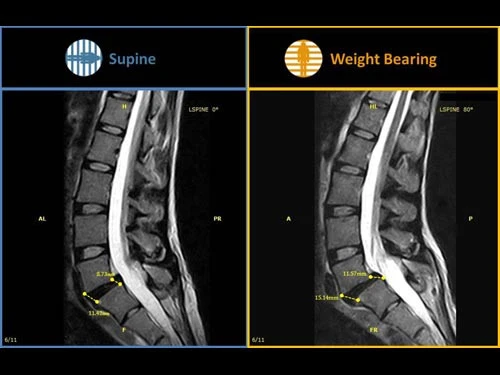

G-scan Brio представляет революционный подход в системах МРТ для всех применений, повышающий точность и надежности диагностики при обследованиях скелетно-мышечной системы. Благодаря опыту, компания Esaote разработала G-Scan, полностью переработанную систему МРТ для исследований при натуральной нагрузки пациента, которая отличается новым дизайном, новыми эргономическими функциями и новыми методами получения изображений Новая система G-scan от компании Esaote является системой магнитно-резонансной томографии, которая позволяет исследовать все суставы, а также отдел позвоночника либо в клиностатическом (лежа на спине) или в ортостатическом (с весовой нагрузкой на ноги) положении, благодаря тому, что магнит и пациент могут вращаться в диапазоне от 0 до 90 градусов. Благодаря специальной конструкции G-scan пациентов можно сканировать в положении натуральной нагрузки, что облегчает диагностику в скелетно-мышечной системы при наличии меняющихся патологий вследствие положения тела, например боли в пояснице. Многие симптомы и патологии возникают или отмечаются, когда пациент находится в положении натуральной нагрузки. Обычные томографы могут не отобразить патологию, связанную с конкретными симптомами, в то время как сканер G-scan предоставляет новую точку обзора, чтобы вы могли точно диагностировать патологию в скелетно-мышечной области, выявленную благодаря применению весовой нагрузки.